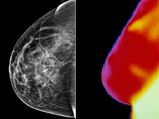

Mammography